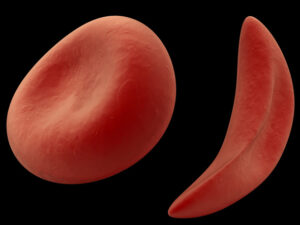

Arterie ostruite

«Con il termine ictus -spiega Linfante- ci riferiamo all’ostruzione a livello cerebrale delle arterie che garantiscono il corretto flusso di sangue. Quando ciò accade le aree a valle del blocco non possono essere sufficientemente irrorate e, con il passare del tempo, vanno in contro a morte cellulare. Intervenire il prima possibile è fondamentale per evitare sia danni permanenti sia, nel peggiore dei casi, la morte».